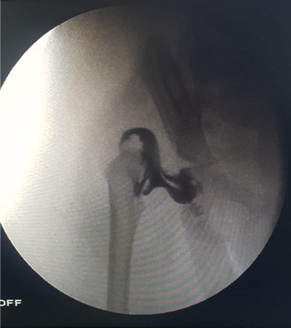

Intra Operative

Arthrogram showing irreducible head with hour glass swelling